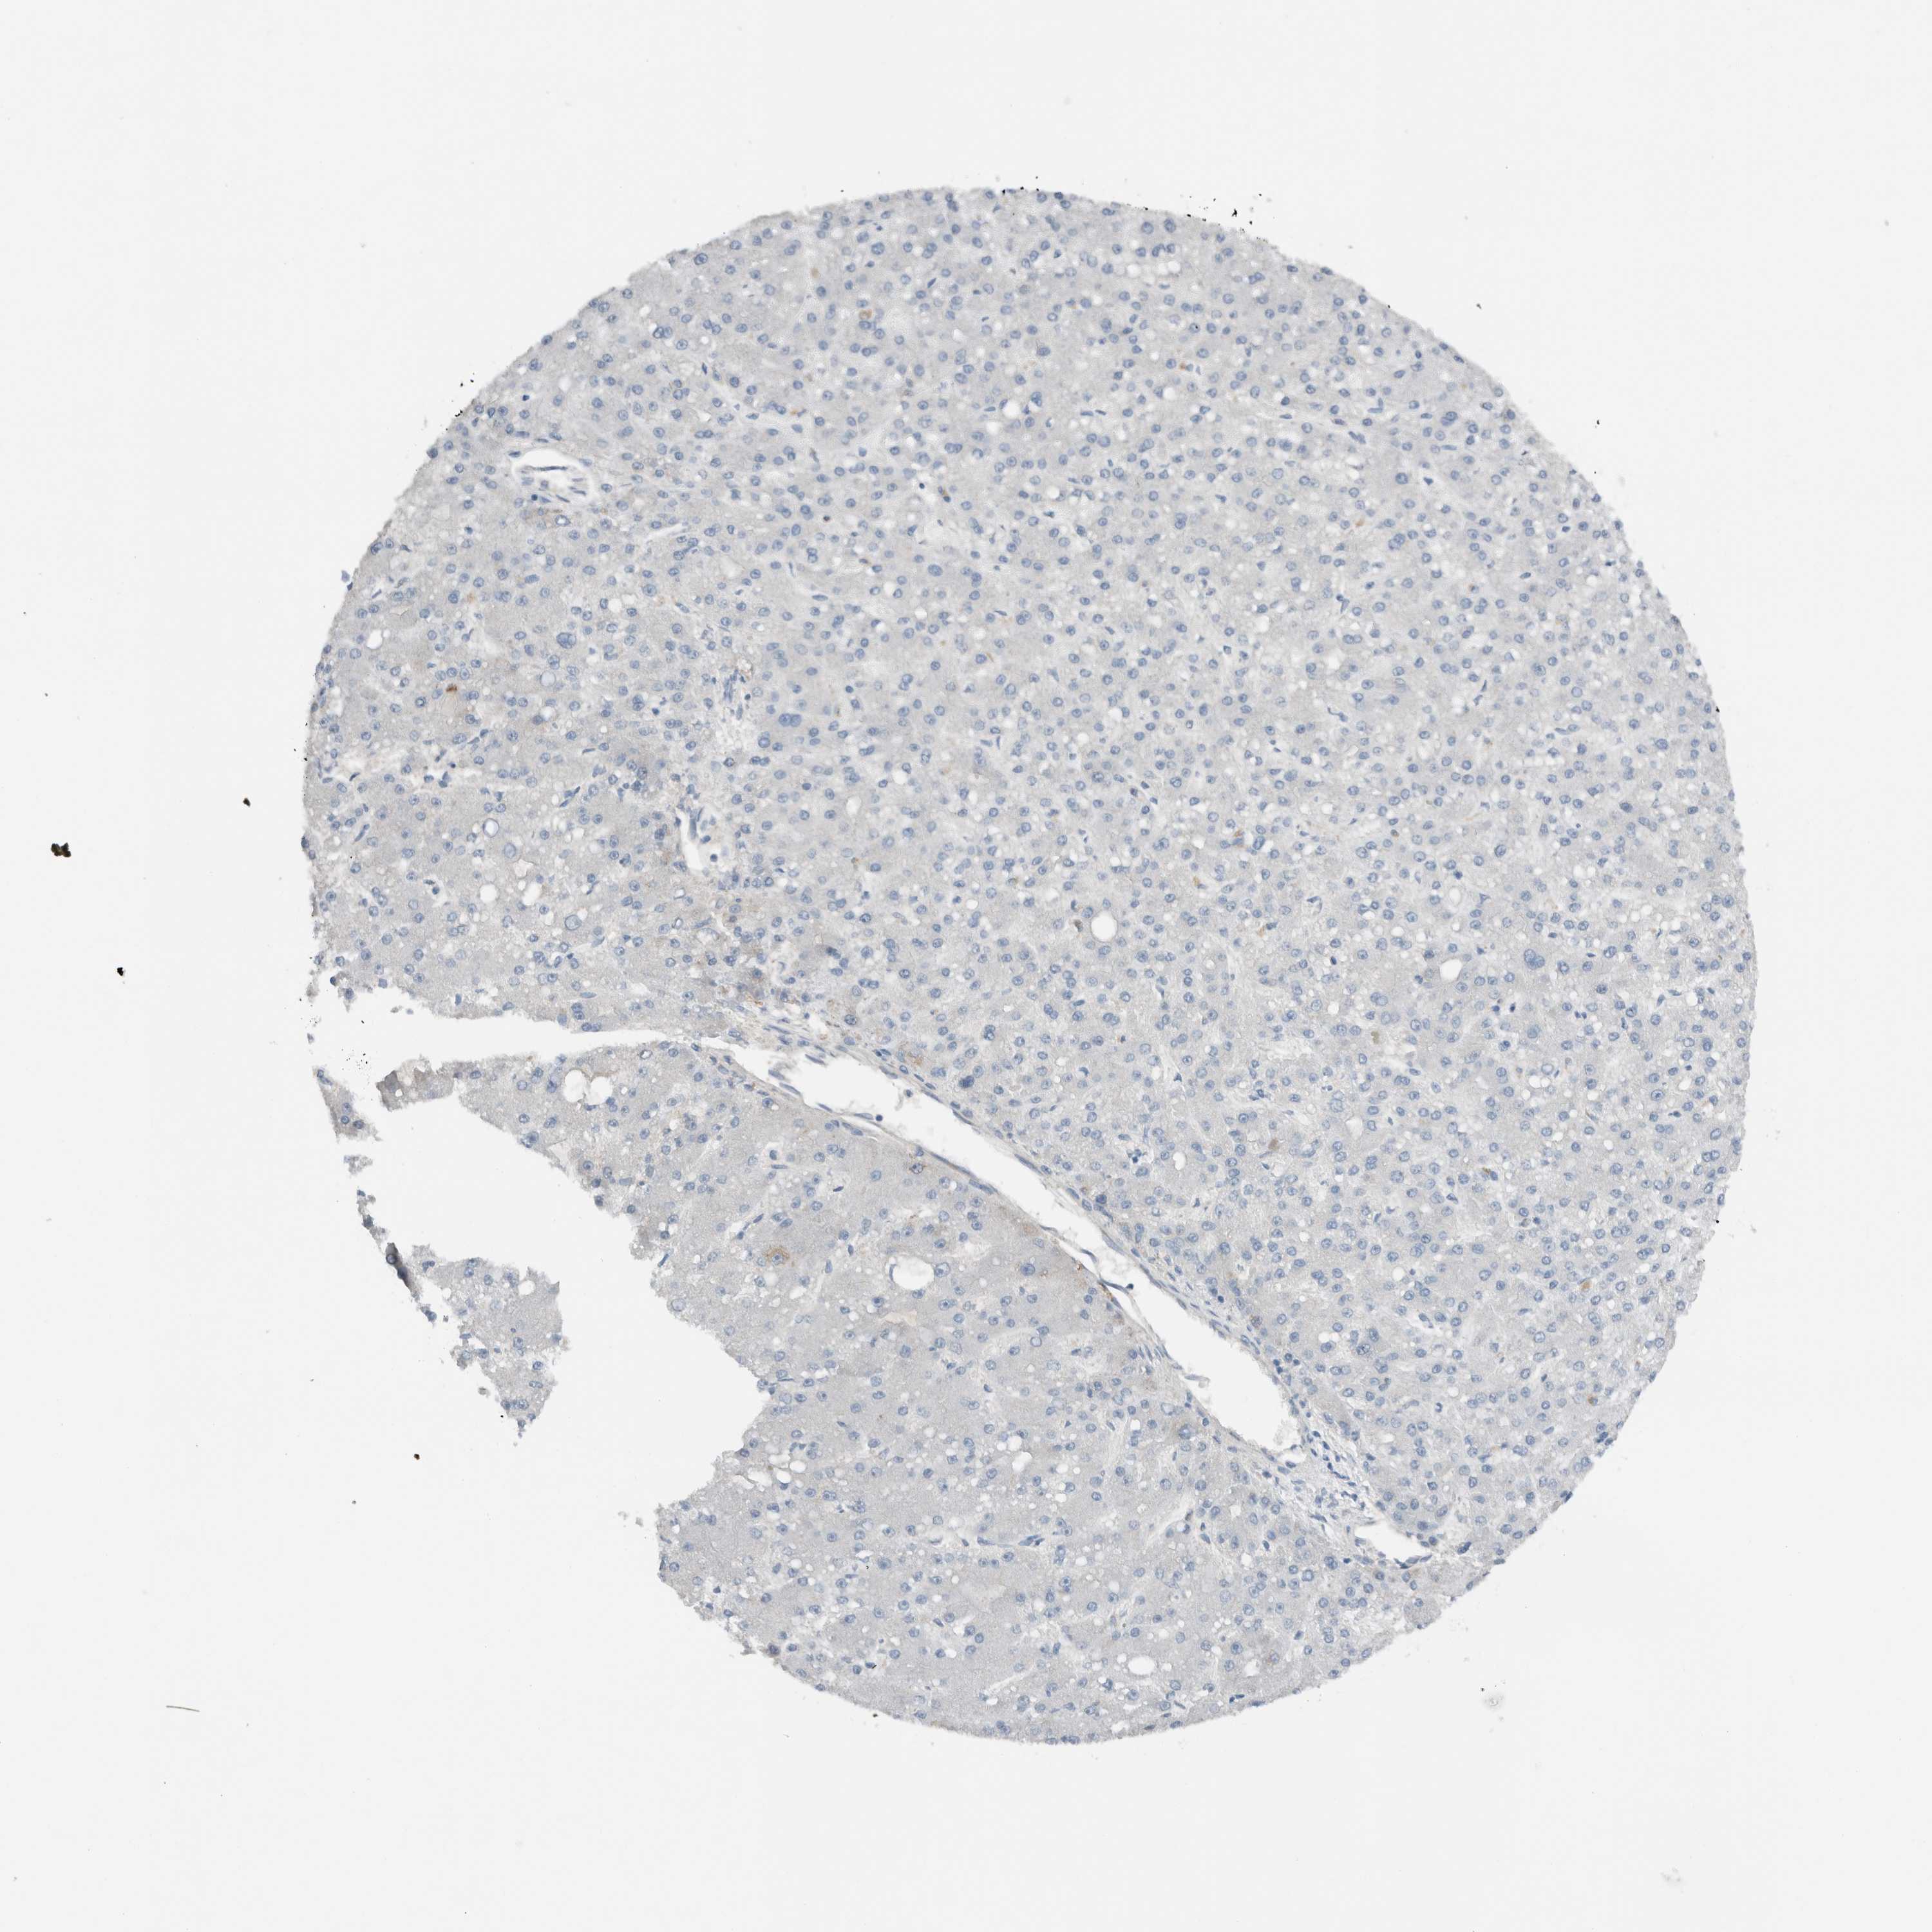

LIVER CANCER - Protein expressioni

A mouse-over function shows sample information and annotation data. Click on an image to view it in a full screen mode. Samples can be filtered based on level of antibody staining by selecting one or several of the following categories: high, medium, low and not detected. The assay and annotation is described here.

Note that samples used for immunohistochemistry by the Human Protein Atlas do not correspond to samples in the TCGA dataset.

Antibody stainingi

Antibody staining in the annotated cell types in the current human tissue is reported as not detected, low, medium, or high, based on conventional immunohistochemistry profiling in selected tissues. This score is based on the combination of the staining intensity and fraction of stained cells.

Each image is clickable and will lead to virtual microscopy that enables deeper exploration of all samples and also displays staining intensity scores, fraction scores and subcellular localization as well as patient and tissue information for each sample.

Antibody HPA023544

Staining

High

Medium

Low

Not detected

Intensity

Strong

Moderate

Weak

Negative

Quantity

>75%

75%-25%

<25%

None

Location

Nuclear

Cytoplasmic/membranous

Cytoplasmic/membranous,nuclear

Cholangiocarcinoma

Carcinoma, Hepatocellular, NOS